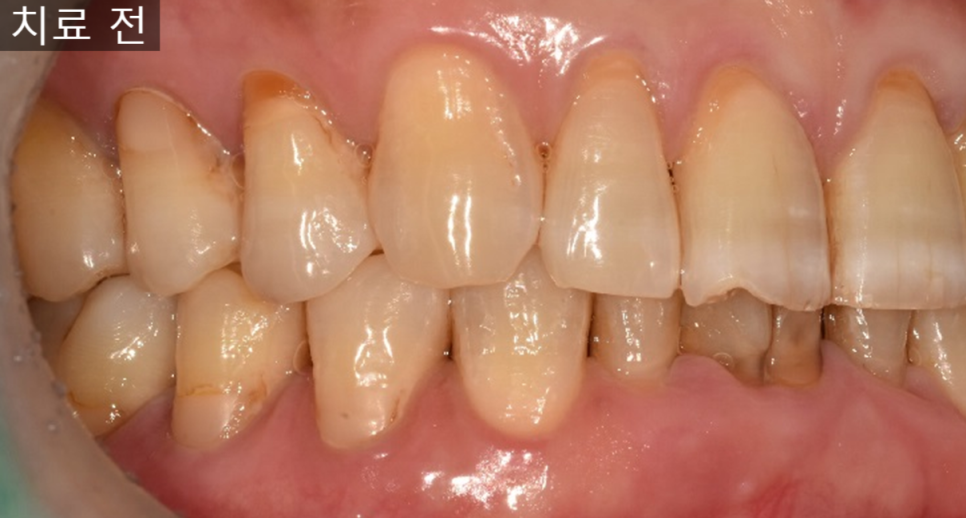

잇몸이 자주 붓고 피가 나며,

어금니가 흔들려 식사가 어려운 상태에서

내원하시는 경우가 적지 않습니다.

이번 케이스는

잇몸이 자주 붓고 출혈이 있으며,

고름이 반복되는 상태였습니다.

아래 어금니 한 부위

이미 크게 파절되어 있었고,

주변 잇몸에는

치석과 염증이 많이 축적되어 있었습니다.